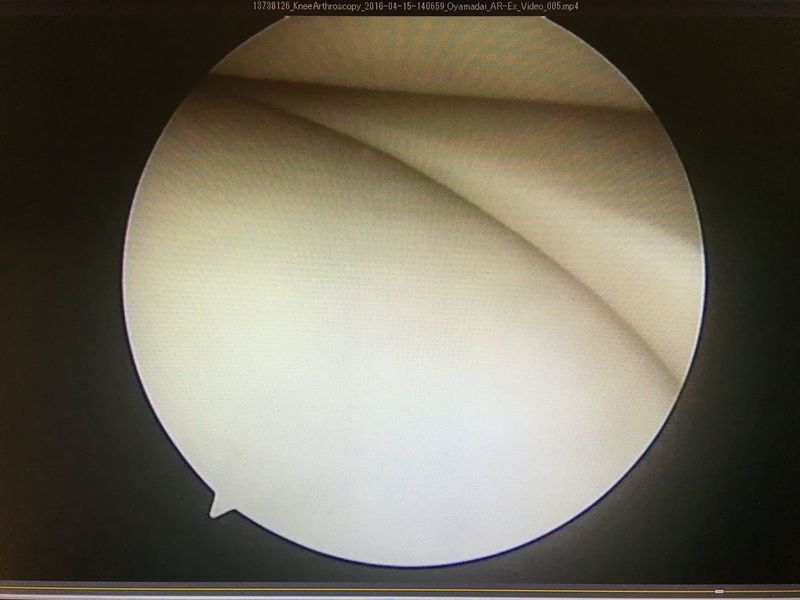

|

ACLは緊張がなく機能していない |

外側半月板は問題なし |

内側半月板は問題なし |

ACL再建

| 大腿骨孔作成 | グラフト挿入 | 再建靭帯 |